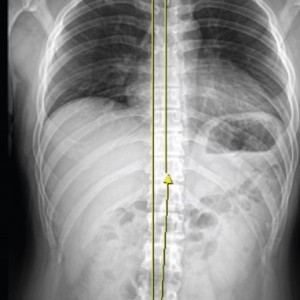

01.

척추

척추측만증 또는 좌, 우 한쪽으로 기울어진 척추로 인해 체중이 한쪽 허리로 집중된다면 장기적으로 체중이 기울어진 쪽 허리에 뼈가 자라거나 퇴행성 변화가 빠르게 진행됩니다.